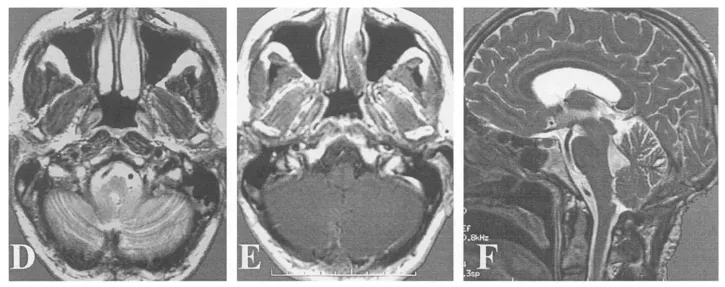

(E)小脑延髓外侧池内结构保持完整,箭头指示右侧椎动脉;

(D-F)术后6个月MR影像证实肿瘤完全切除。

(F)术后6个月患者临床状态良好。